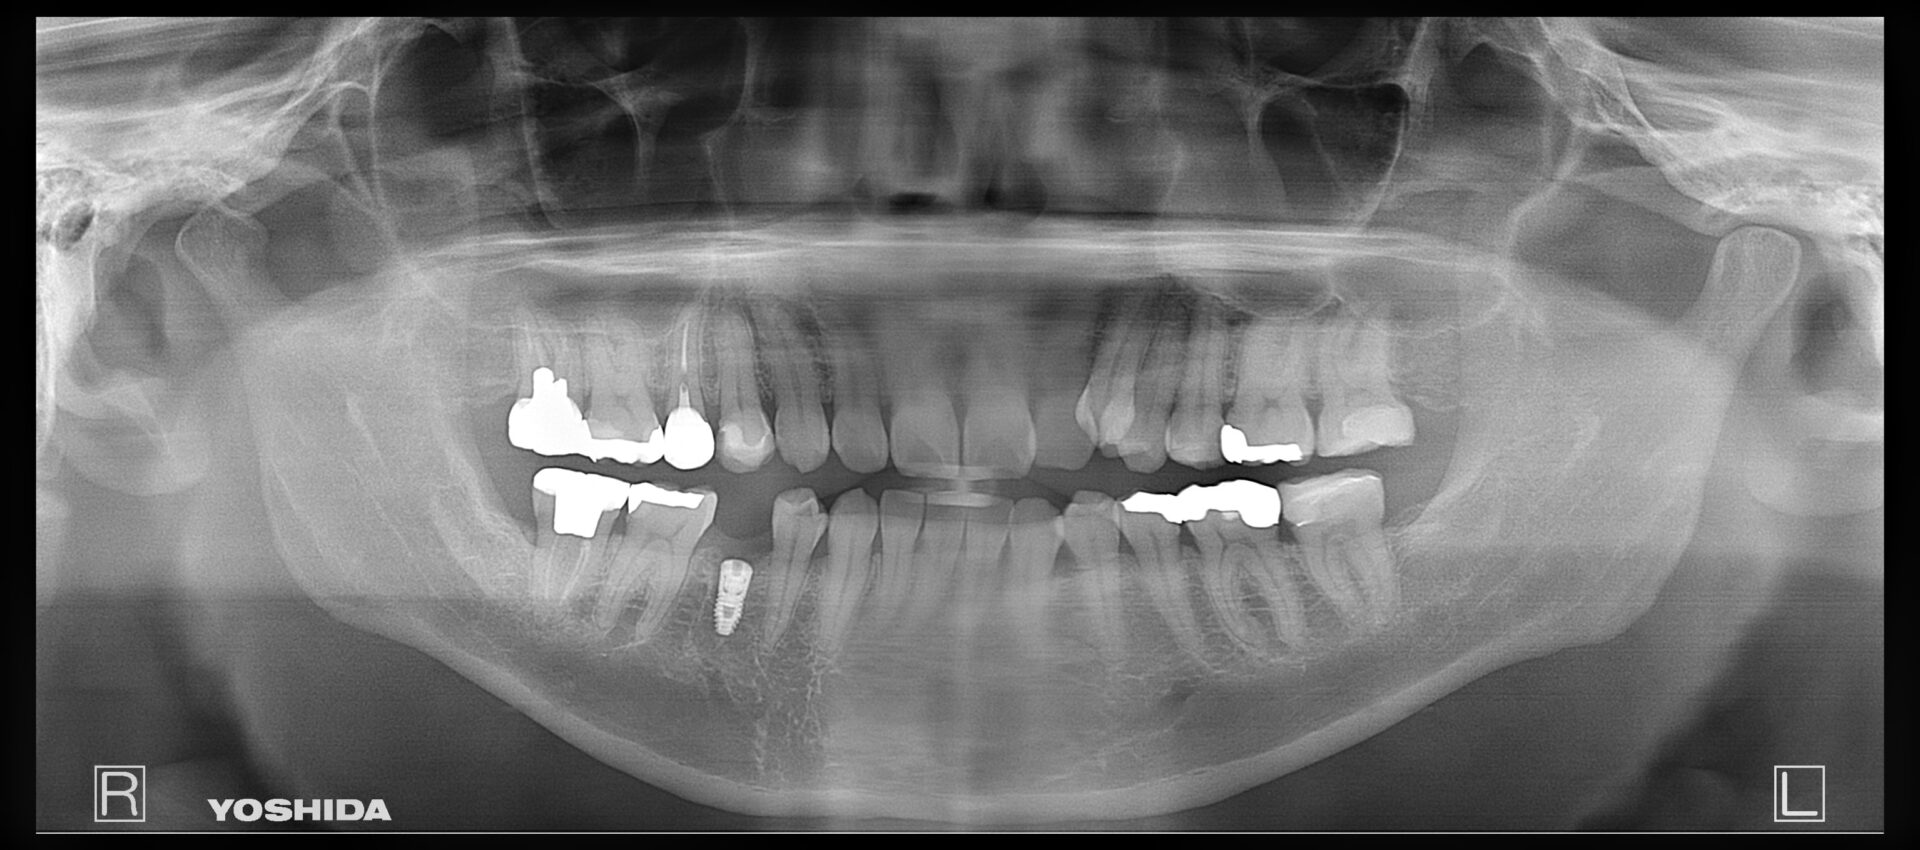

50代男性

R2.7

画像

R5.5

治療部位 左下6,7

費用 約700000円

治療期間 約6ヶ月

痛み、腫れを感じておりレントゲンを撮影、歯が破折している可能性がありました。

被せ物を外しヒビが確認されなければ根管治療で歯を残せる可能性があること、

ヒビがあった場合は抜歯になってしまうと説明しました。

このケースは残せる状態ではなく抜歯という選択になりましたが、できるだけ患者様のご希望に寄り添い、

治療計画をご提案できるよう最善を尽くしております。